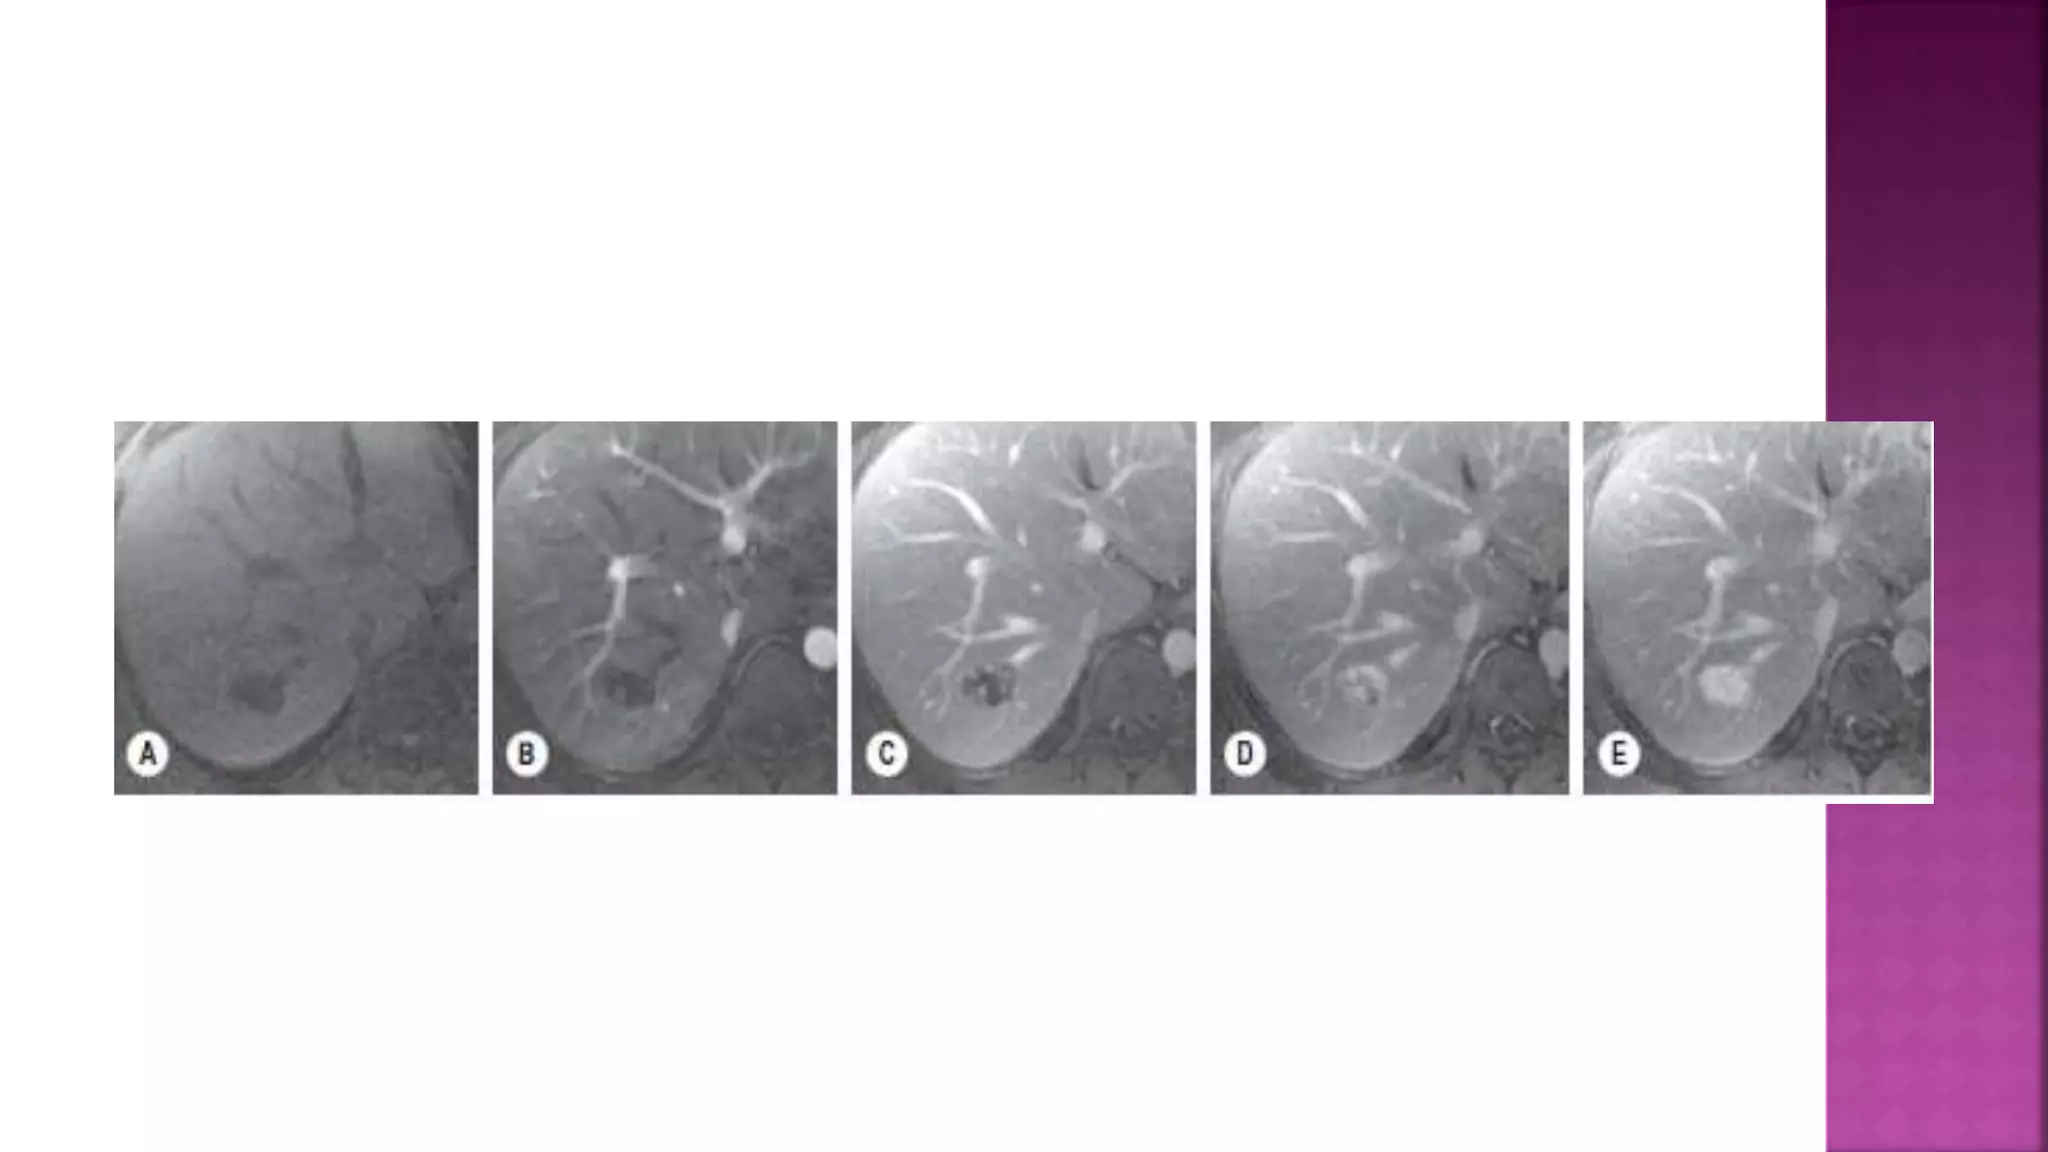

On single-shotT2w FSE imaging the lesion is barely visible (A) but better demonstrated

(arrowheads) on fat-suppressed multi-shotT2w FSE (B).

There is avid arterial phase enhancement (C), becoming isointense in the portal (D) and delayed phases (E). A

central scar is evident on some of the images (arrowhead), which enhances on the delayed image (E).